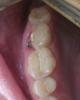

monozubik Опубликовано 23 марта, 2009 Поделиться Опубликовано 23 марта, 2009 (изменено) Около года назад на вышеуказанном зубе (семерка верхняя) был обнаружен пульпит. Зуб был депульпирован с последующей установкой пломбы (если не ошибаюсь филтек). На протяжении всего срока после лечения зуб меня больше не беспокоил. Два дня назад, во время еды, зуб сломался (( Раскололся он на две половинки. В результате одна половинка, более большая, статична, а другая шаталась. Доктором было принято решение удалить эту шатающуюся часть, чего и было проделано и я отправлен домой до нового визита к стоматологу. С оставшейся половиной будем решать что делать после заживления ранки. Примерно понимаю что вариантов два:* Удалить и установить имплант * Попытаться восстановить Почитав форум, возникли вопросы:1 Реально ли восстановить зуб без обтачивания соседних ? С сохранением ессно необходимой прочности.2 Уместен ли в сложившейся ситуации метод CEREC или всеж т.к. корень один удалили уже поздно реставрировать этим методом ? Реставрации CEREC прочны? 3 Если так и оставить, зуб сожрет кариес ? Или Кариес мертвичиной не питается ? Прокомментируйте пожалуйста, очень хочется услышать мнения нескольких специалистов дабы выбрать оптимальный метод лечения. Спасибо заранее за советы.Фотографии с цифровика прилагаю, пока они только такие. В следующий раз у доктора заберу ренгеновский. Изменено 23 марта, 2009 пользователем monozubik Ссылка на комментарий